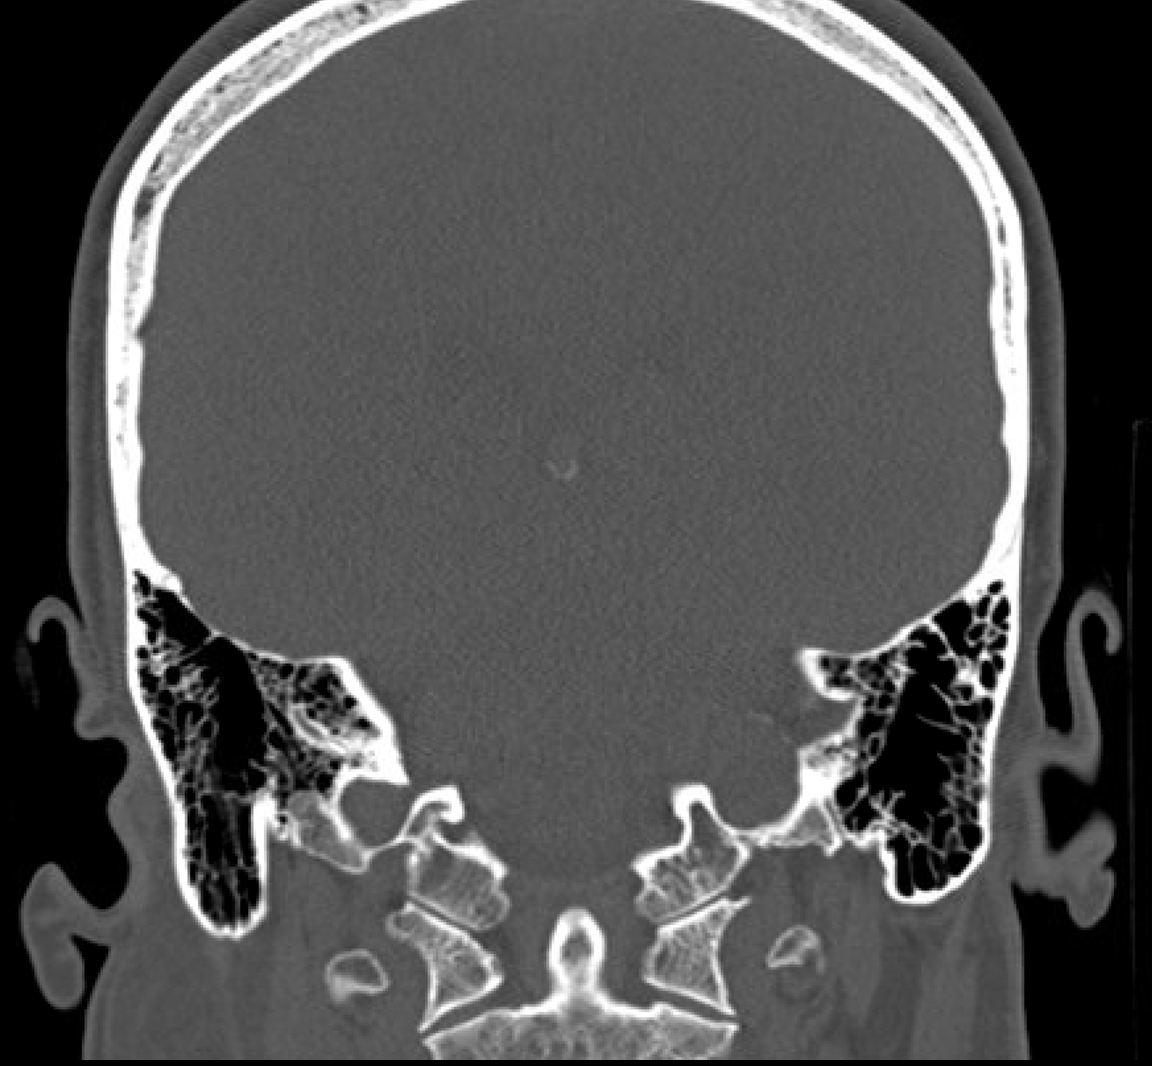

The mastoid bone, with its honeycomb-like structure, is part of your temporal bone. It plays a significant role in the drainage and ventilation of the ear. However, when an infection from the middle ear extends into the mastoid bone, it can lead to a condition known as mastoiditis, necessitating medical intervention, often in the form of mastoid surgery.

Mastoid surgery, medically known as mastoidectomy, is a procedure performed to remove infected air cells within the mastoid bone caused by untreated or severe middle ear infections. The goal is to eradicate the disease, prevent its recurrence, and in some cases, help restore hearing.